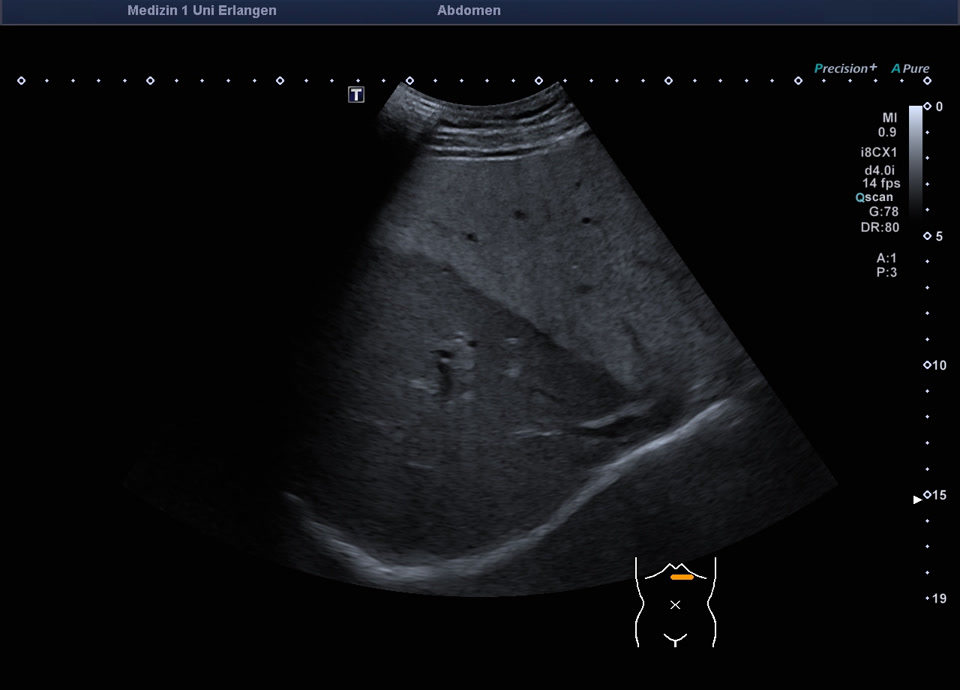

Focal fatty infiltration

Fokale Mehrverfettung